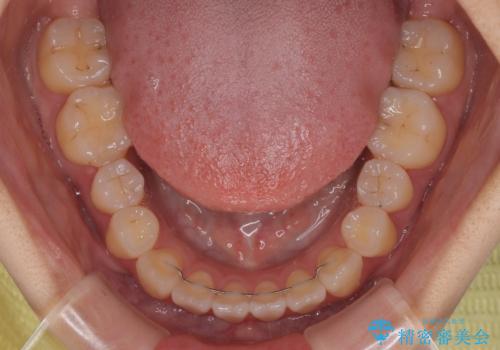

オープンバイトは舌の突出癖により誘発され、治療後も突出癖が残っている容易に後戻りしてしまいます。

治療期間を短縮するためにも、舌突出癖の改善が極めて重要となります。

特にインビザラインではIPRという歯と歯の間を削る処置を多用するため、後戻りによりスペースが生じやすくなるため、治療初期段階での舌のトレーニングが必須となります。